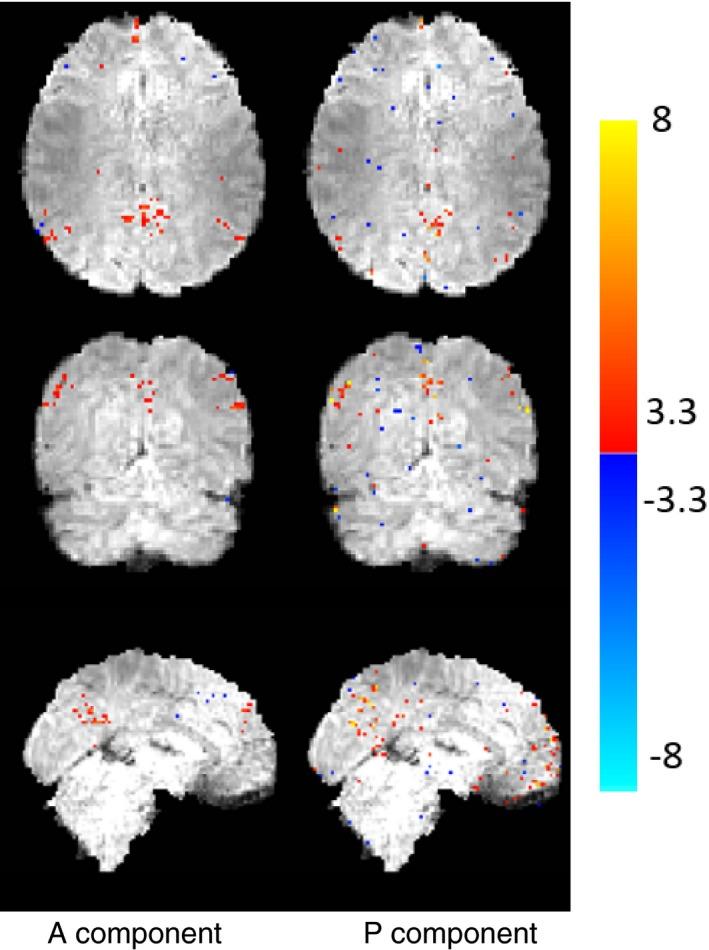

The proposed approach decomposes the fMRI signal into a component which has a fixed rank and a component consisting of a sum of periodic signals which is sparse in the temporal Fourier domain. Data reconstruction is performed by solving a constrained problem that enforces a fixed, moderate rank on one of the components, and a limited number of temporal frequencies on the other. Our approach is coined PEAR - PEriodic And fixed Rank separation for fast fMRI.

This paper presents PEAR, an undersampled fMRI reconstruction approach based on decomposing the fMRI signal to periodic and fixed rank components. PEAR results in reconstruction with higher fidelity than when using a fixed-rank based model or a conventional Low-rank + Sparse algorithm. We have shown that splitting the functional information between the components leads to better modeling of fMRI, over state-of-the-art methods.